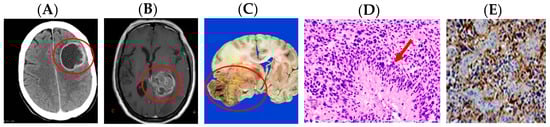

- Wikipedia. Glioblastoma Multiforme. Available online: https://commons.wikimedia.org/wiki/File:Glioblastoma_(1).jpg (accessed on 18 July 2017).

- Wikipedia. Glioblastoma GFAP. Available online: https://commons.wikimedia.org/wiki/File:Glioblastoma_GFAP.jpg (accessed on 27 March 2017).

- Wikipedia. Oligodendroglioma. Available online: https://commons.wikimedia.org/wiki/File:Oligodendroglioma_001.jpg (accessed on 18 July 2017).

- Wikipedia. Glioma Gross 4. Available online: https://www.wikidoc.org/index.php/File:Glioma_Gross_4.jpg (accessed on 18 July 2017).

- World Health Organization Classification of Tumors. A Public Database of Human Cancers. Available online: http://www.pubcan.org/cancer/18/oligodendroglioma-nos/histopathology (accessed on 27 March 2017).